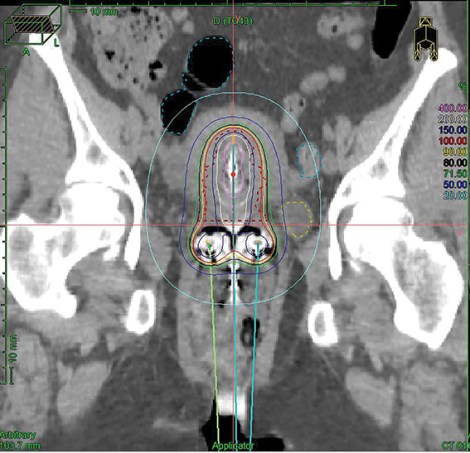

Genesis Cancer Care is the only WA clinic to use the ground-breaking brachytherapy to treat cervix cancer, where an applicator inserted into the uterus delivers a high burst of concentrated radiation.

“Lots of studies have shown that if you combine the external radiotherapy with the brachy treatment, there is a higher survival rate,” says Dr Sia.

“It’s a very effective complementary treatment.”